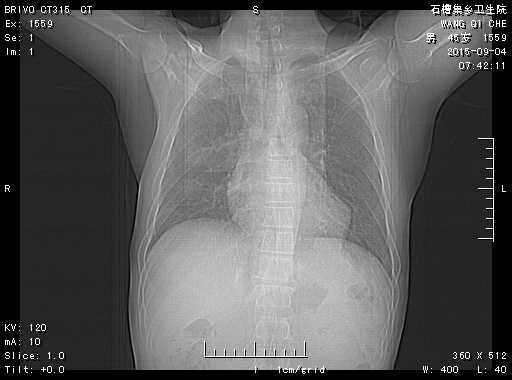

CT51112:患者 m45 有HIV病史 咳喘月余

请各位老师指点

机遇性感染改变。

符合机遇性感染改变

间质性炎症,艾滋病最多就是肺部感染,机遇性感染多见

间质发到肺炎